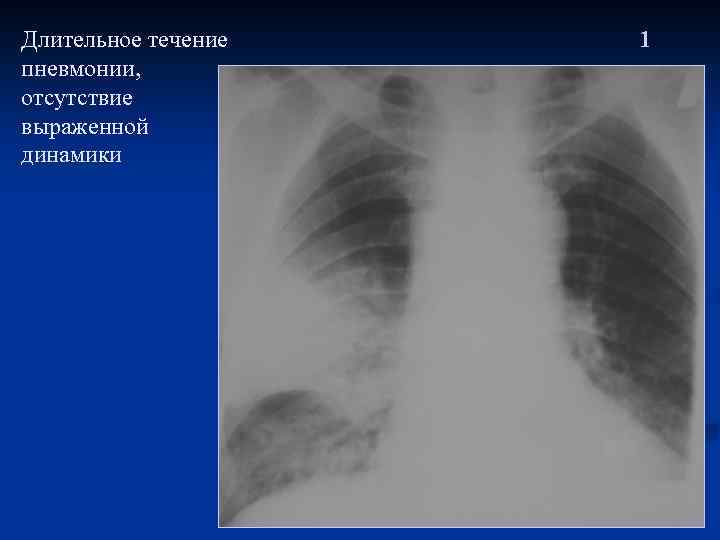

Длительное течение пневмонии, отсутствие выраженной динамики 1

Через 10 дней